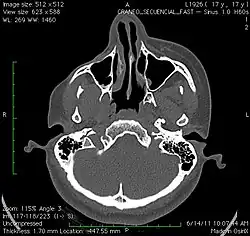

A 3D, soft tissue reconstruction of a CT scan of a 17-year-old girl with Parry Romberg syndrome.

-

CT scan 3D bone reconstruction of a 17-year-old girl with Parry Romberg syndrome.